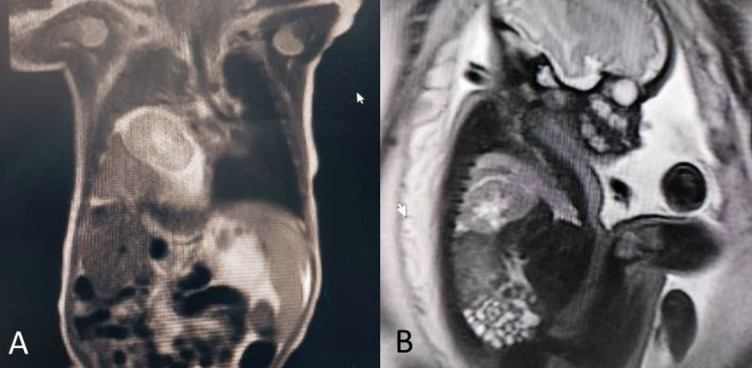

Material and methods: We report the case of a 28-week fetus in which, on ultrasound imaging, a mass was observed displacing the heart and lung in the right hemithorax, which was was confirmed by magnetic resonance (MR) to be an ectopic intrathoracic kidney (ITEK). After birth, the neonate was approached by laparoscopy to place a mesh in continuity with the diaphragm, leaving the kidney in the abdomen, with good evolution. A search was conducted in the PubMed, Embase and Cochrane databases for cohorts, case reports and case series of prenatal diagnosis of intrathoracic kidney in the fetus. Information was retrieved regarding design, population, imaging diagnosis, treatment and prognosis.

Results: The search identified 8 studies that met the inclusion criteria, reporting a total of 8 cases. Ultrasound diagnosis showed ectopic intrathoracic kidney associated with diaphragmatic hernia in all the subjects. Fetal magnetic resonance imaging (MRI) was also used in 5 cases.